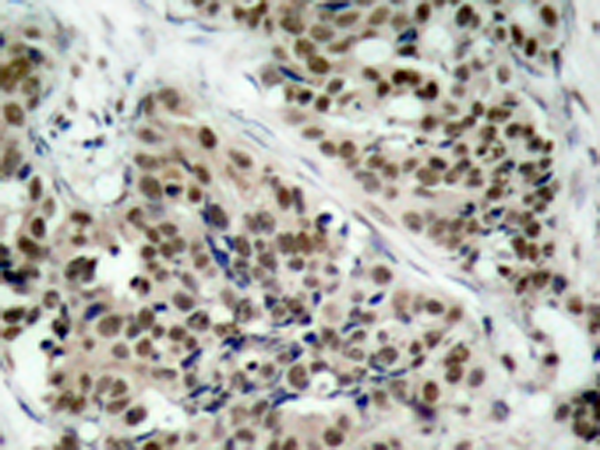

IHC positive control:

Human breast carcinoma

IHC Recommend dilution:

50-100